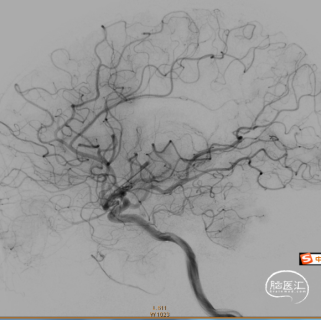

Syphonet®取栓支架应用SWIM技术抽拉结合取栓一次,造影确认脑血流完全恢复,mTICI 3级,成功一把再通。

术后24小时复查头颅CT未见颅内出血。

患者术后24小时拔除气管插管,神志清楚,精神可,言语欠清,双侧瞳孔等大等圆,直径3mm,对光反射灵敏,颈软,心律齐,未闻及杂音,双肺呼吸音稍粗,未闻及干湿性啰音,右侧上下肢体肌力4级,左侧肌力5级、肌张力正常,双侧巴氏征阴性。术后24小时 GCS:15分,NIHSS:2分,mRS:1分。